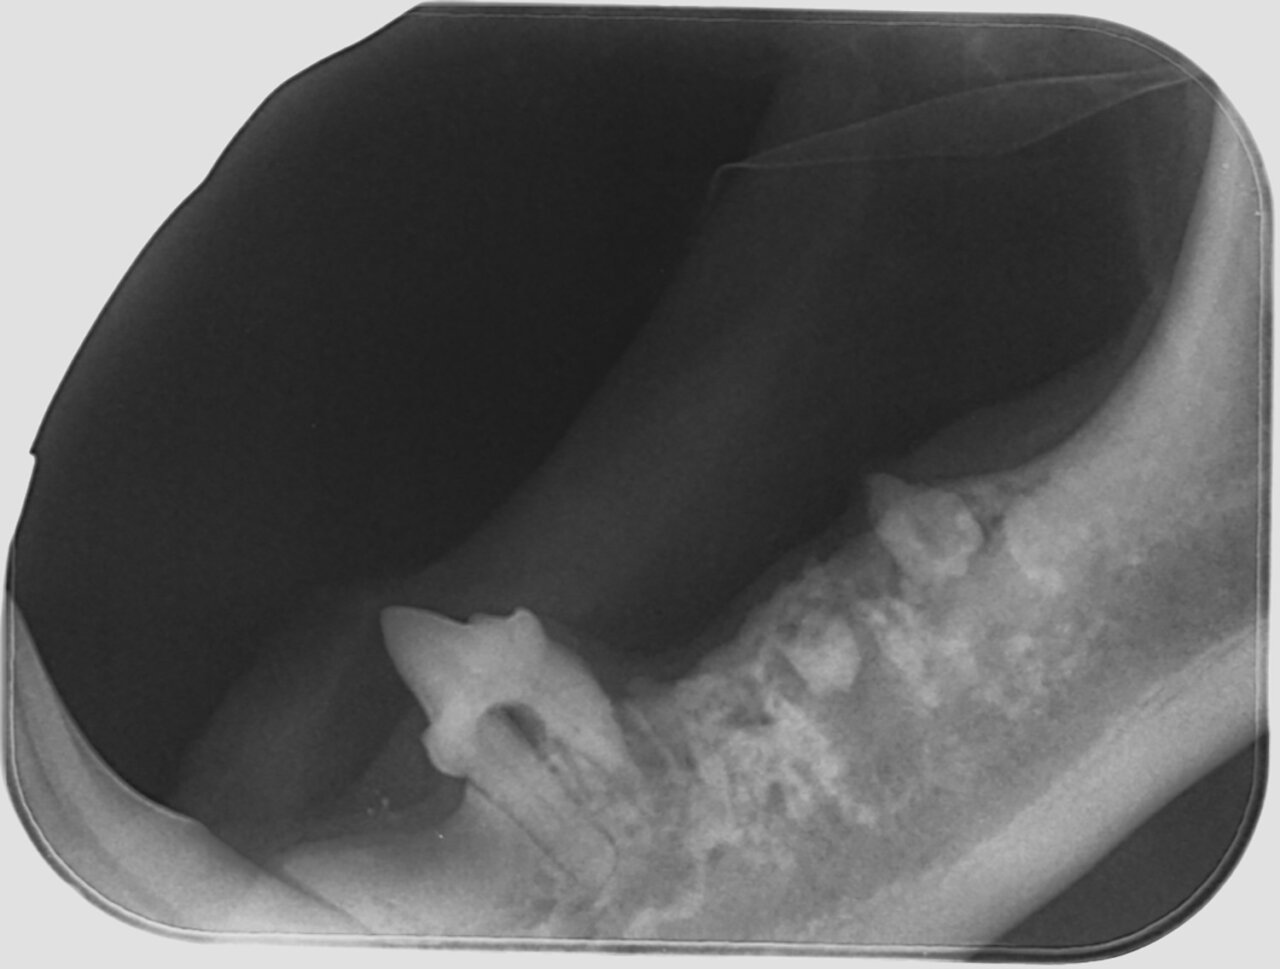

Alteración en el número y posición de los dientes

Ausencia dental

Cuando en una exploración visual de la boca observamos una ausencia dental debemos hacer una radiografía que nos indique la causa, que puede ser de origen genético o deberse a alteraciones sufridas durante las primeras etapas del desarrollo dental o a lo largo de la vida del animal.

A nivel radiológico nos podemos encontrar con varias situaciones:

- Ausencia del diente porque no se ha formado (agenesia).

- El diente no ha erupcionado por estar ectópico (fuera de su área anatómica).

- El diente está incluido o impactado (cuando no logra erupcionar o lo hace parcialmente por diferentes causas).

También puede ser debida a la pérdida dental (por EP, por ejemplo) o a fracturas de corona en las que quedan restos de estructuras dentales bajo la encía. Por tanto, dependiendo de ello, decidiremos el enfoque terapéutico que tomaremos en cada paciente con ausencia dental. (imágenes 14-17).

Aumento del número de dientes

La presencia de dientes supernumerarios también debe ser estudiada mediante la radiología intraoral. La causa principal es genética y la radiología nos permitirá valorar su naturaleza, si se trata de un diente definitivo o la falta de exfoliación de dientes deciduos (en caso de no tenerlo claro a la inspección visual). En este último caso, podremos valorar el estado de la raíz y su relación con el diente permanente, aspectos que debemos tener en cuenta a la hora de realizar su extracción (imágenes 18 y 19).